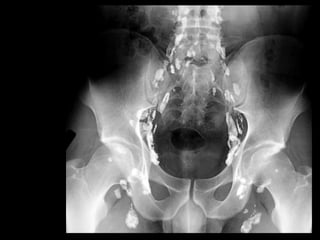

Pelvis

Lymphatic Drainage of Pelvis

 4 Primary groups lie in relation to great blood

vessels

 External, internal & common iliac vessels

 Sacral nodes lie in relation to sacrum

 All drain into common iliac nodes  lumbar

nodes

 Common iliac nodes directly or indirectly drain

lower limb, lower part of abdominal wall &

pelvic organs

Lymphatic Drainage of Pelvis & Perineum